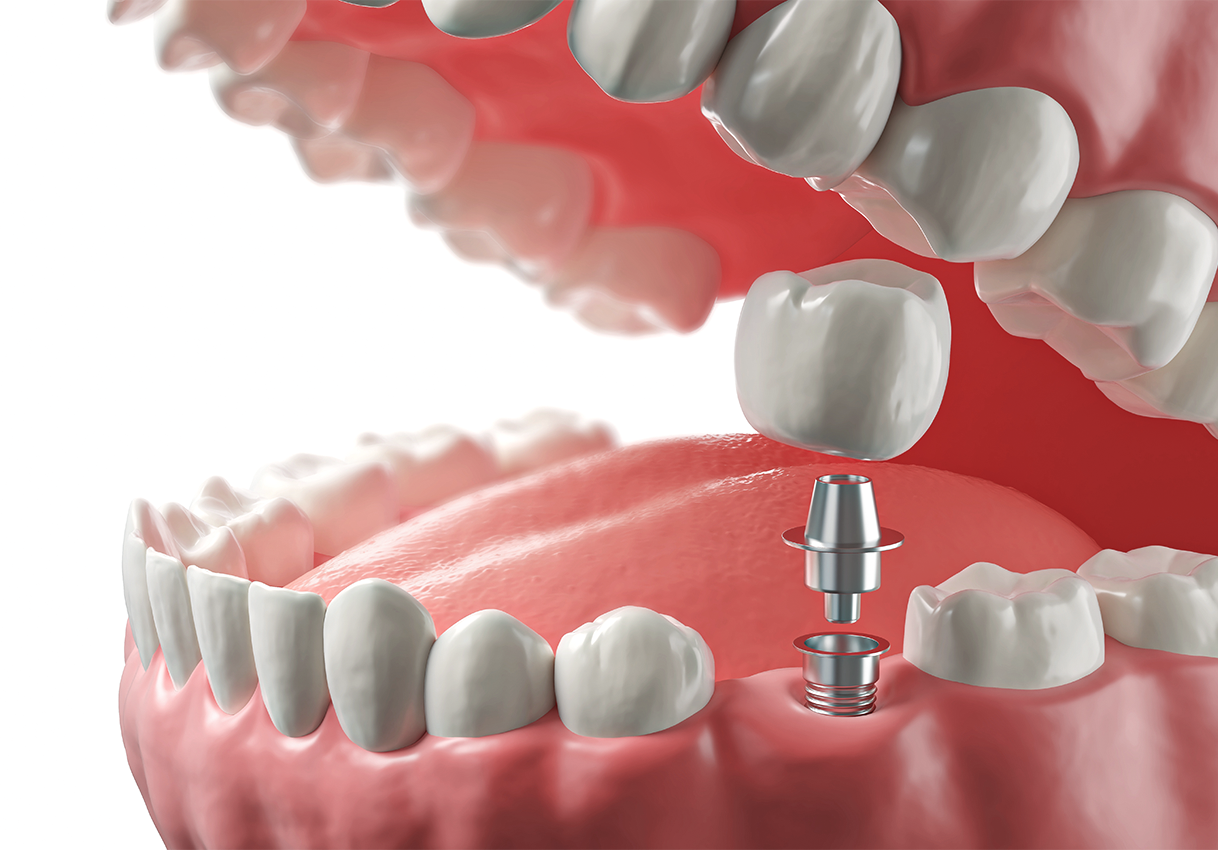

임플란트 주위를 둘러싼

뼈가 튼튼해야

임플란트가 튼튼하게 고정되어 오랫동안 안정적으로 사용할 수 있습니다.